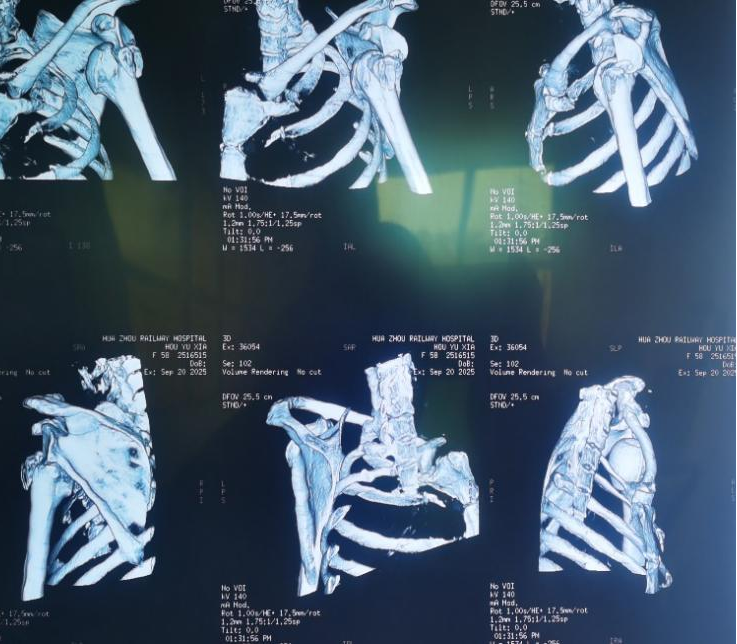

患者术前三维重建检查可见肱骨大结节粉碎性骨折